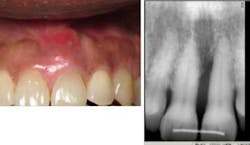

Mrs. High Anxiety has returned for all postop appointments this time around. Her abscess has resolved and a small amount of bone regeneration is noted on the eight-month postop radiograph. If the bone fill is not better at one year, a retreatment of the site will be suggested. Tissue height, which was a major esthetic concern, has remained at an acceptable level for the patient.

Mrs. High Anxiety after treatment.